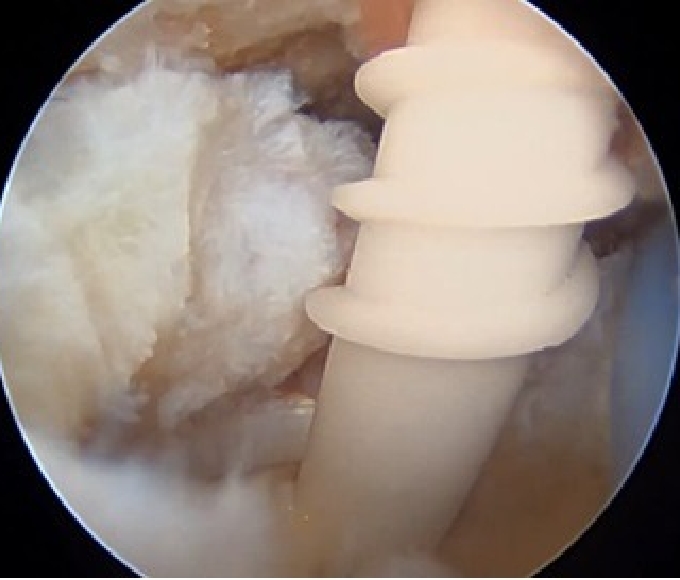

U字型の中断裂

上腕骨頭(大結節Footprint)が露出してしまっている。